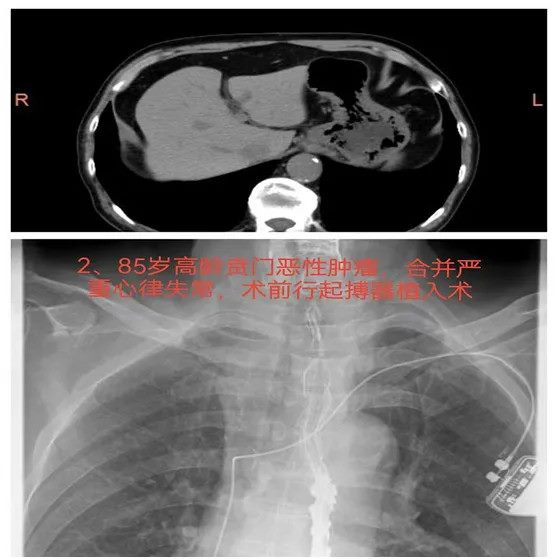

02高龄胃癌,复杂病例中的手术选择

患者,男性,85岁,因“腹胀、食欲不振”就诊。胃镜检查提示贲门部占位,病理诊断为贲门腺癌。患者既往有心率失常、房颤史,并接受过经皮冠状动脉介入治疗(PCI)及起搏器植入手术。由于年龄较大且存在多重基础疾病,术前评估和围手术期管理面临巨大挑战。入院后,团队制定了详细的术前准备方案,并在全体专家的协作下,顺利完成了近端胃癌根治术及双通道吻合术。手术过程中,密切监测患者心功能,确保手术安全。术后患者恢复良好,腹部症状得到明显缓解。

难点总结:该病例的难点在于患者年龄高、基础病多,尤其是心律失常及心功能不全,增加了手术的风险。如何在保证手术效果的同时,精细管理围手术期的心脏功能,成为术前决策和术中操作的核心挑战。

推荐理由:该病例不仅成功解决了高龄患者的多重基础疾病挑战,还通过双通道吻合术有效预防了术后反流并发症的发生。术前全面评估和术中细致操作确保了手术效果,术后患者恢复良好,为类似病例提供了重要的治疗经验,尤其是在高风险患者中,能够有效改善术后生活质量,降低并发症风险。